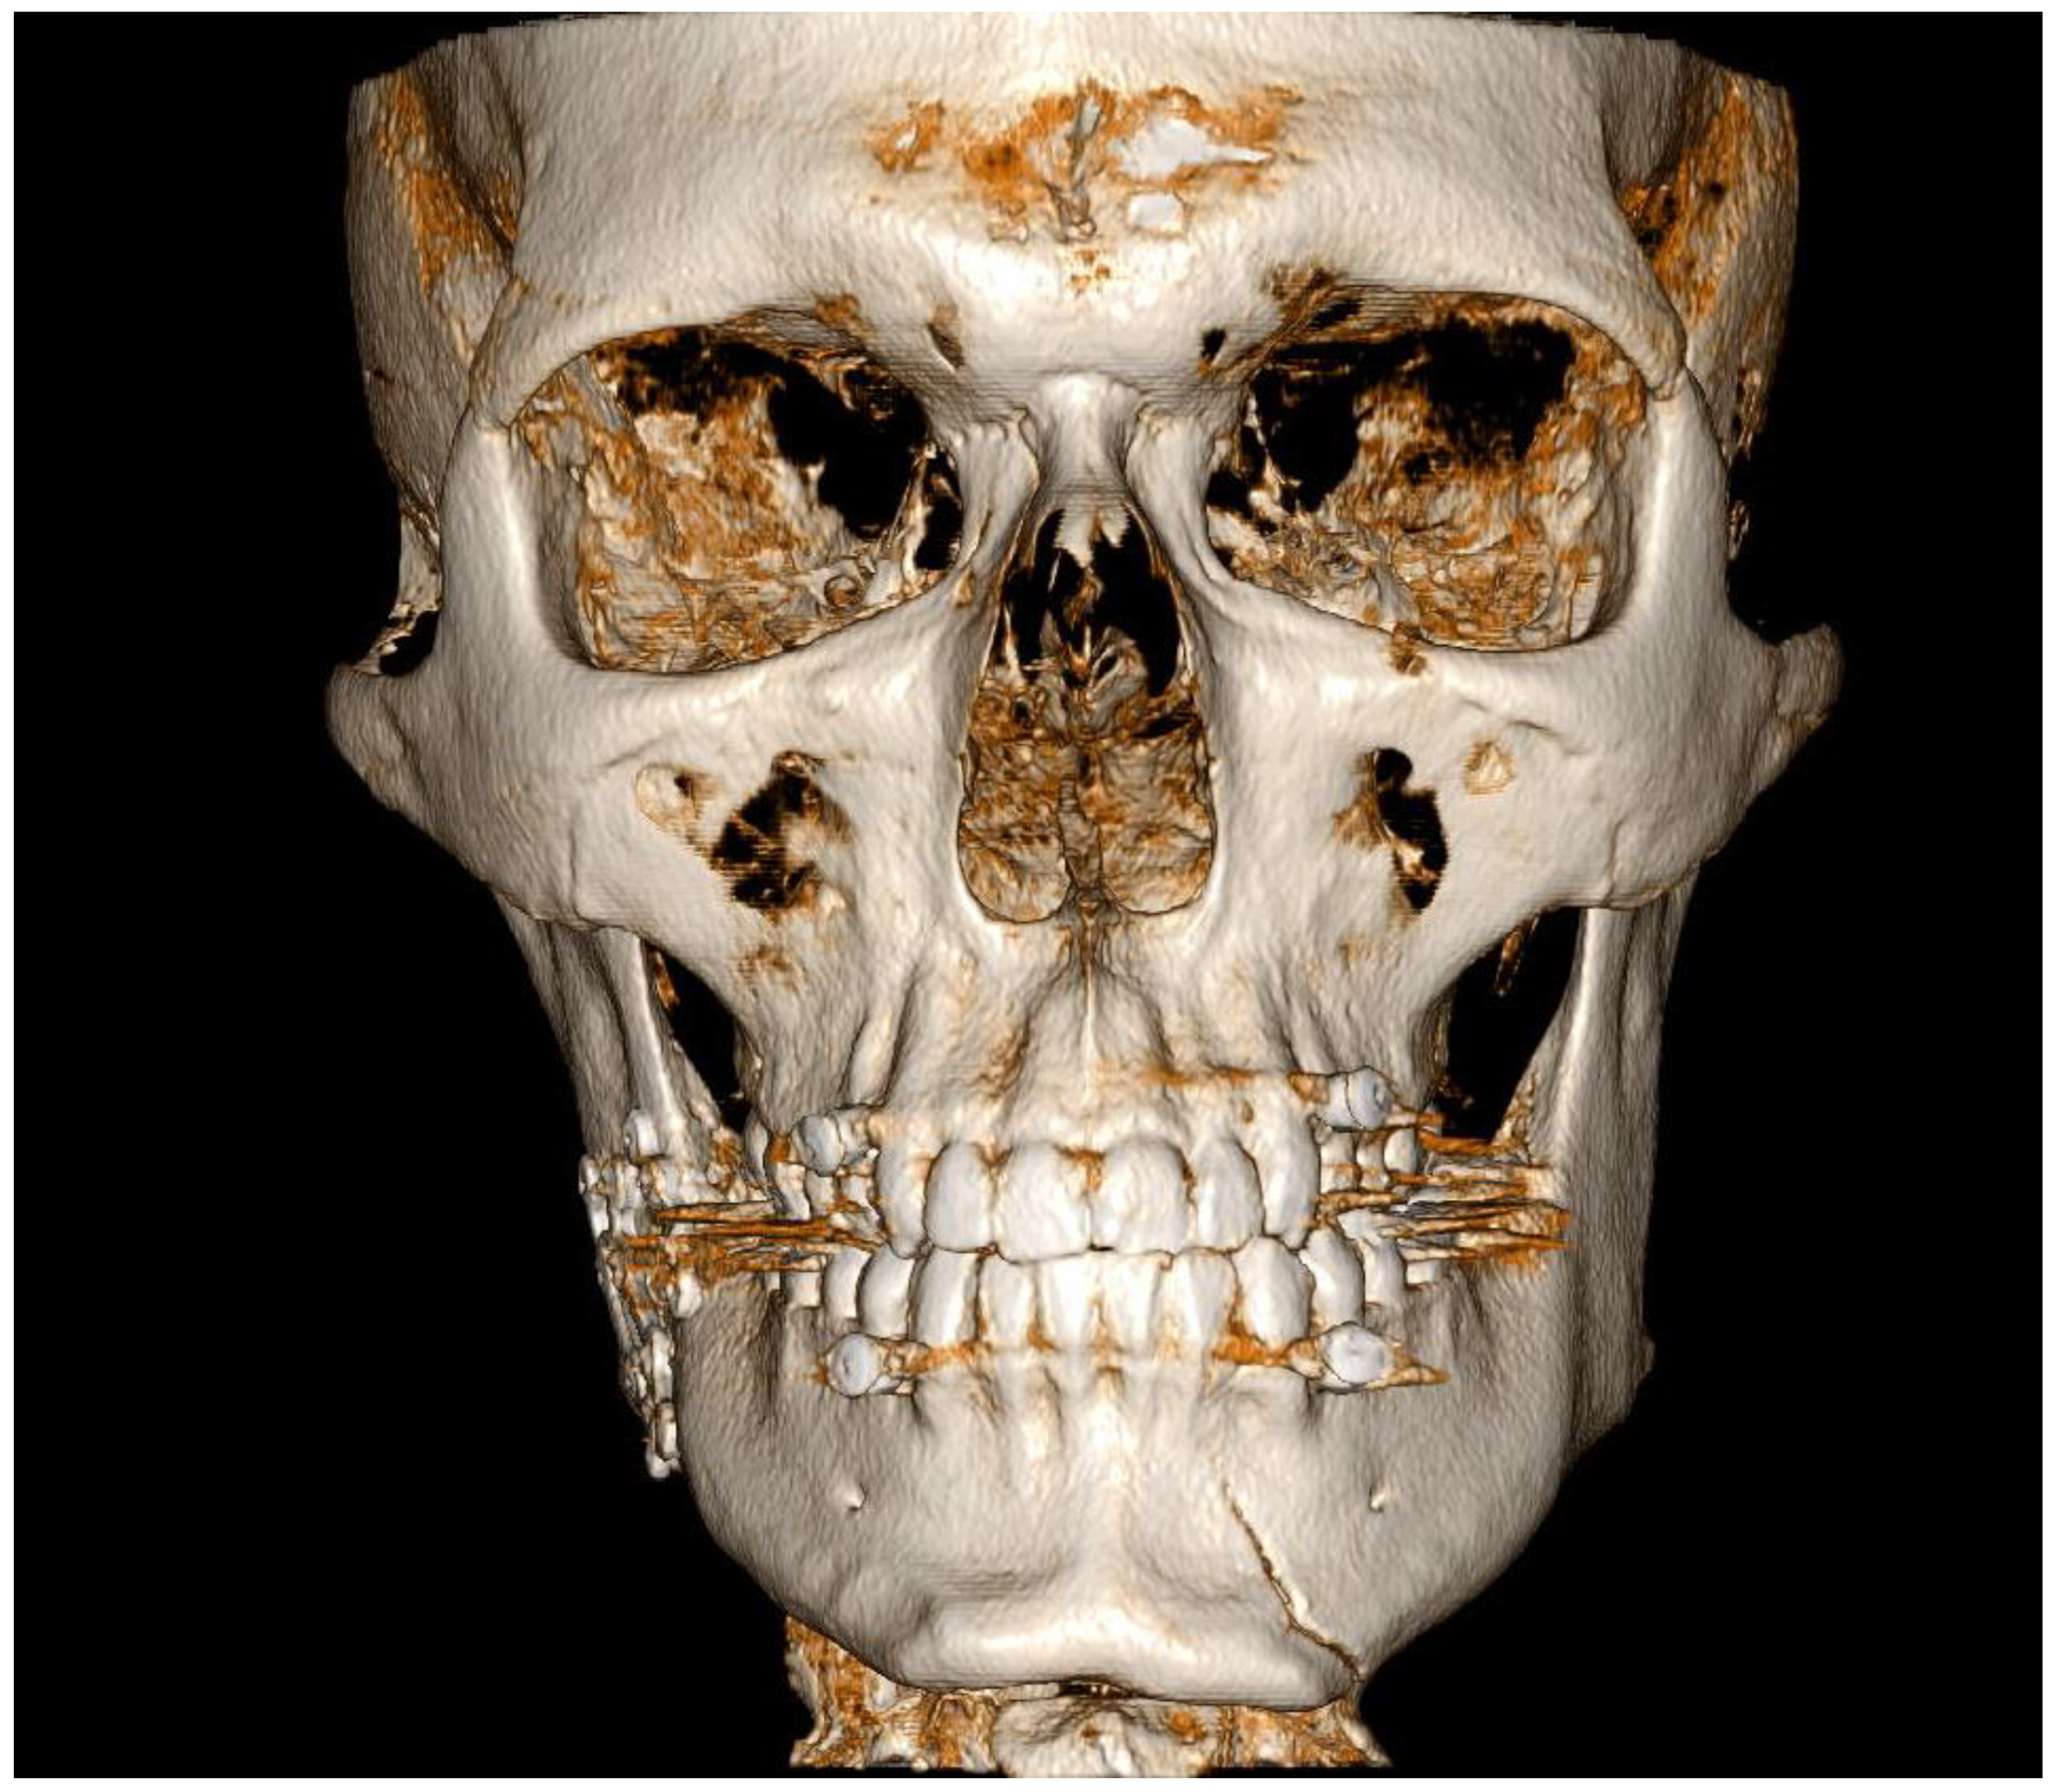

3.1. Case 1